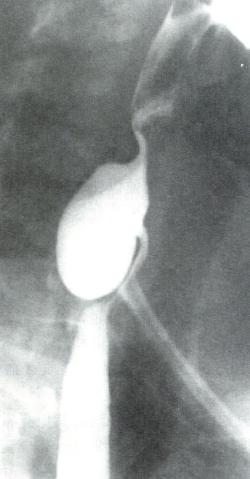

食管X线吞钡

为诊断Zenker憩室的首选检查(图2.6)。

图2.6 Zenker憩室的X线表现。憩室囊位于食管后方。